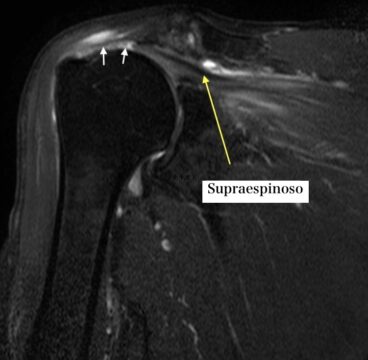

Por lo general, el médico evalúa el hombro mediante la exploración física y pruebas de imagen como la resonancia magnética (Figura 2) o la ecografía, para comprobar si existe una lesión del manguito rotador.

Se ha descrito que la ecografía es útil para el diagnóstico de los desgarros del manguito rotador, y la resonancia magnética también se utiliza de forma amplia. La elección de la prueba depende del contexto clínico y de la pregunta diagnóstica concreta[3][4].

La evaluación clínica también incluye la historia del problema, la palpación y pruebas dirigidas a músculos concretos. Por ejemplo, las pruebas del supraespinoso ayudan a valorar la fuerza de elevación, las del infraespinoso la fuerza de rotación externa y las del subescapular la fuerza de rotación interna.